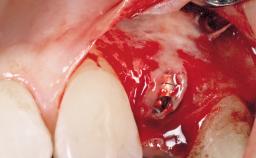

This 43-year-old male patient, a non-smoker, came to our practice because of a fracture of tooth 12 caused by a bicycle accident. Due to the combined para- and infrabony crown and root fracture, tooth extraction, and subsequent implant placement were suggested to the patient as the therapy of choice. The patient had high esthetic expectations with regard to the treatment outcome and asked for an immediate fixed provisional restoration. His individual esthetic risk profile summed up to a medium esthetic risk.

Placement Protocol Immediate implant placement

Tooth Site Maxillary incisor or canine

Socket Morphology Single-root socket

Socket Integrity Sufficient, with intact bone walls